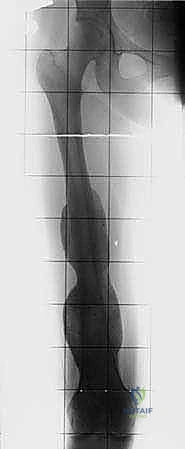

| الأشعة المقطعية (CT Scan) | تقييم أدق للقشرة العظمية والتكلسات داخل الورم. كما يُستخدم لتصوير الصدر (CT Chest) للبحث عن انتشار الورم للرئتين. | يساعد في التخطيط ثلاثي الأبعاد لقص العظم وتصميم الطرف الاصطناعي. |

- الأطراف الاصطناعية المعيارية (Modular Megaprostheses): هي أطراف مصنوعة من التيتانيوم وتأتي في قطع وأحجام مختلفة يمكن تركيبها معاً أثناء الجراحة لتناسب الطول المفقود من عظم المريض بدقة.

- الأطراف المخصصة (Custom-made Implants): في الحالات شديدة التعقيد، يتم استخدام الطباعة ثلاثية الأبعاد (3D Printing) لتصميم وتصنيع طرف اصطناعي خاص يتطابق تماماً مع تشريح المريض.